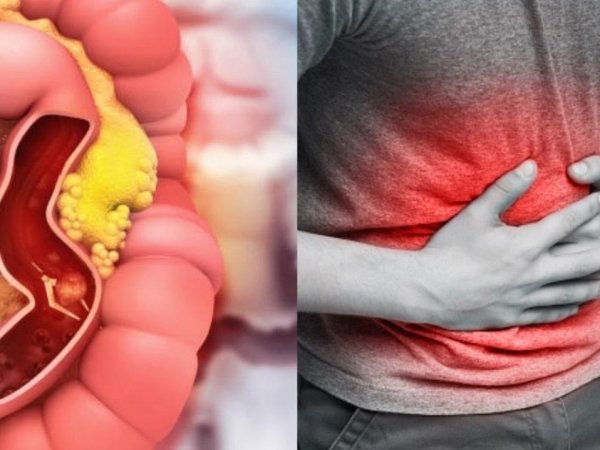

Cáncer de Colon es el segundo mas frecuente en el país

Generalidades de Cáncer de Colon y Recto